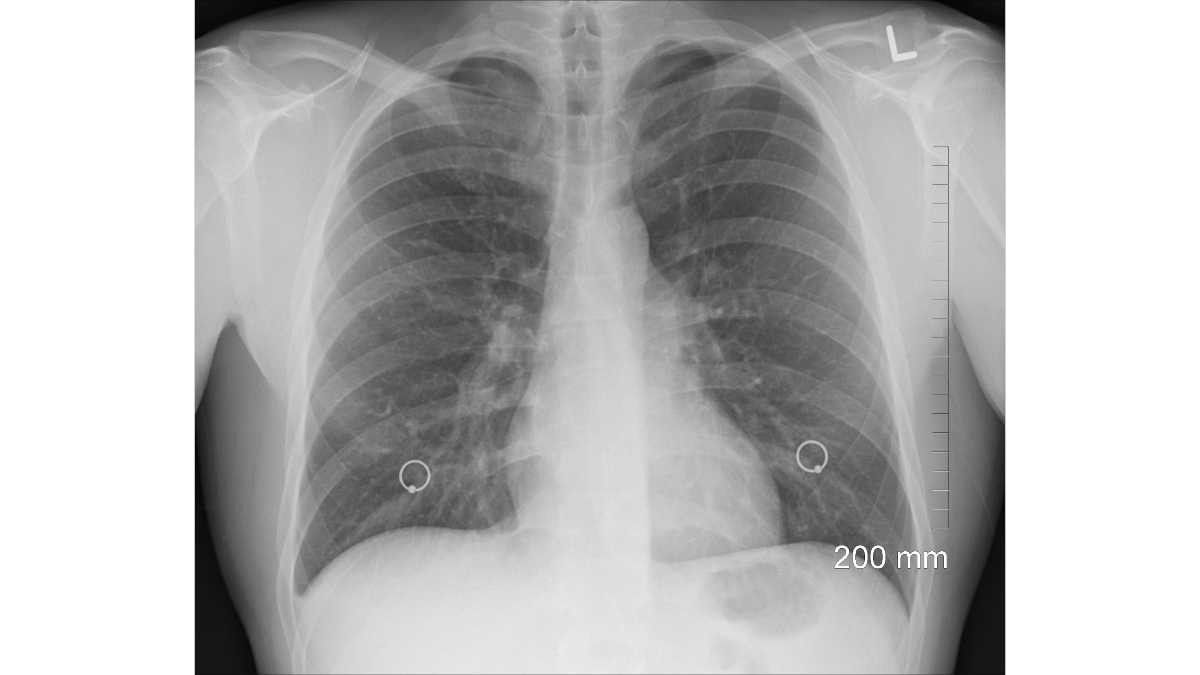

Kerusakan paru akibat tertusuk patahan iga bahkan dapat menyebabkan komplikasi gangguan pernapasan, salah satunya yaitu pneumothorax. Berdasarkan Mayo Clinic, pneumothorax merupakan kondisi ketika udara bocor dan terjebak di rongga pleura, yaitu ruang di antara paru-paru dan dinding dada.

Pneumothorax berbahaya, karena kondisi ini bisa membuat paru-paru mengempis, namun tidak bisa mengembang. Hal ini pada gilirannya menyebabkan paru kolaps.

Ketika paru kolaps, gejala yang bisa muncul tidak hanya sesak napas dan nyeri dada. Penderitanya juga akan mengalami kulit membiru, jantung berdebar, batuk, keringat dingin, serta lemas.